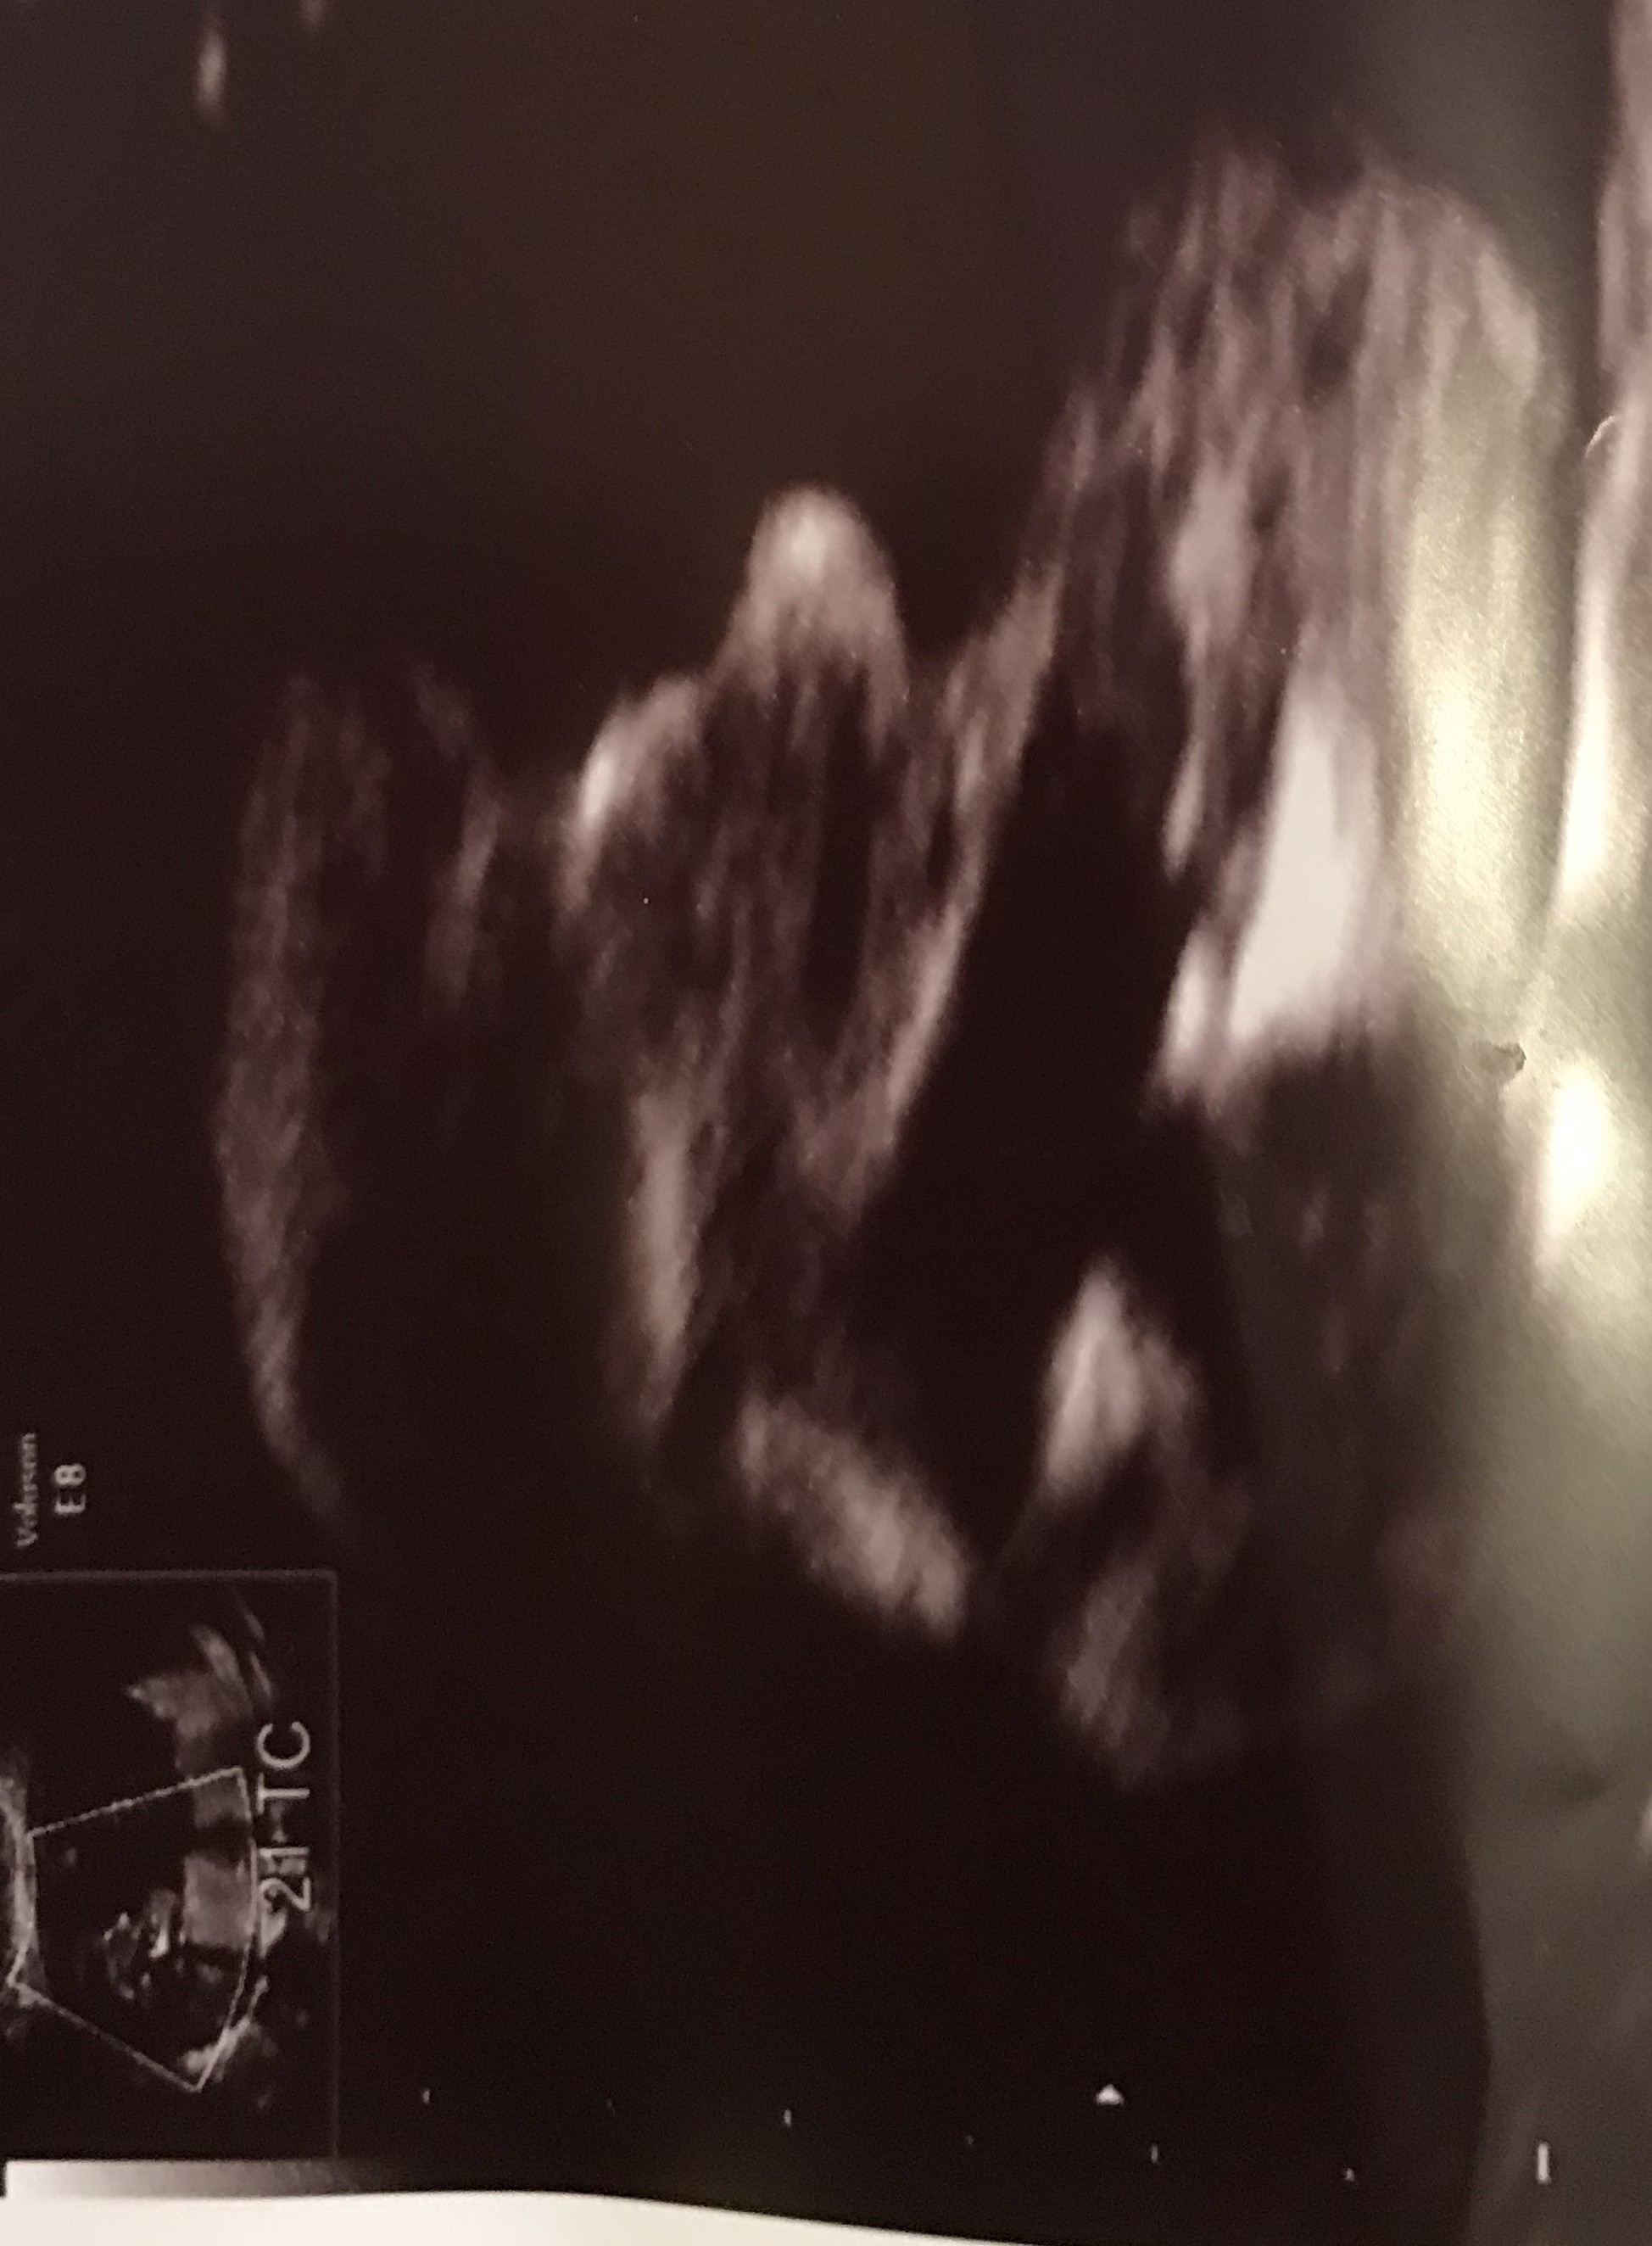

U mnie widać dość wyraźnie płeć - chłopczyk, stwierdzony najpierw w 20 tc, a następnie podczas badań prenatalnych w 21 tc. Myślę, że w dzisiejszych czasach pomyłki lekarzy co do płci już są bardzo rzadkie. Chociaż to jest moja druga ciąża po 15 latach (mam już syna) i teraz ciążę przechodziłam zupełnie inaczej niż pierwszą (mdłości, zle samopoczucie itp.), to wyglada na to, że pozostanę jedyną kobietą w domu ;-)

Do 17 tc nie można było odczytać płci, ponieważ maluszek się ukrywał (ułożenie główką do dołu i pokazał pośladki). Dopiero podczas wizyty w 20 tc (zaznaczam kiepski sprzęt) ginekolog się uśmiechnął i pokazał ujęcie z boku, gdzie widziałam charakterystyczne jąderka i coś krótkiego, „pływającego” - siusiak